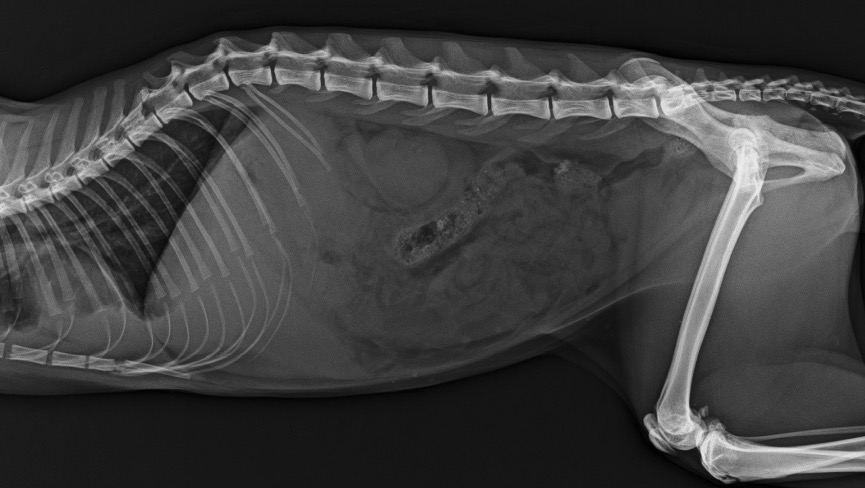

El veterinario que lo atendió sospechaba entre un cuerpo extraño y PIF, debido a que encontraron líquido libre en su radiografía. Le realizaron una cirugía exploratoria, en la cual se descartó presencia de cuerpo extraño, intususcepción y masa abdominal, quedando viva la sospecha de Peritonitis Infecciosa Felina (PIF), una enfermedad muy agresiva, que basta realizar una búsqueda en google para alarmarse.